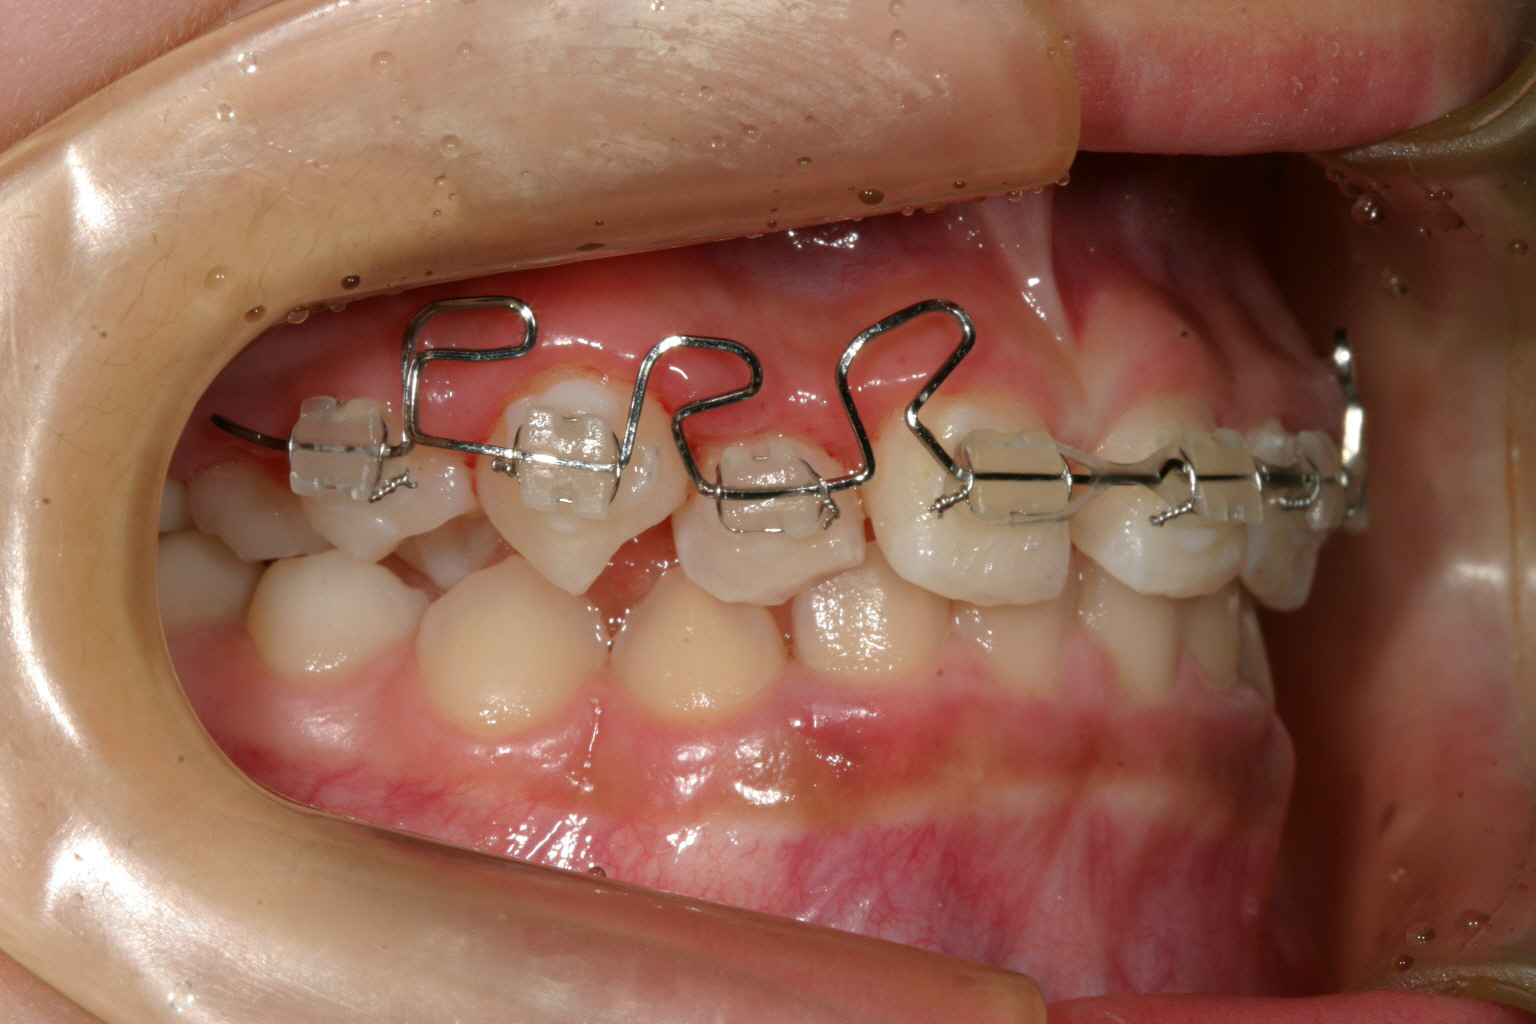

横から見るとこんな感じです。 2か月後です。

まだ10歳の子供さんの為顎の骨も柔らかくマルチループワイヤーで短期間で治療する方法を試みました。

私は子供さんの場合口腔清掃に不安点があるため、ワイヤーを使っての長期の治療は避けるべきだと考えています。

又、通常小児矯正は永久歯が全部萌える迄かなりの期間を要する為、あまり手を付けないのですが、放っておくと下顎が前に出てる為上顎骨の成長を阻害する可能性が有るという意味合いで下顎による上顎骨のブロックされてるのを開放してあげる意味でも必要だと判断いたしました。

今回の場合はマルチループワイヤーを使用することにより短期間で終了致しました結果お母さまにも通院回数も少なくて喜ばれました。